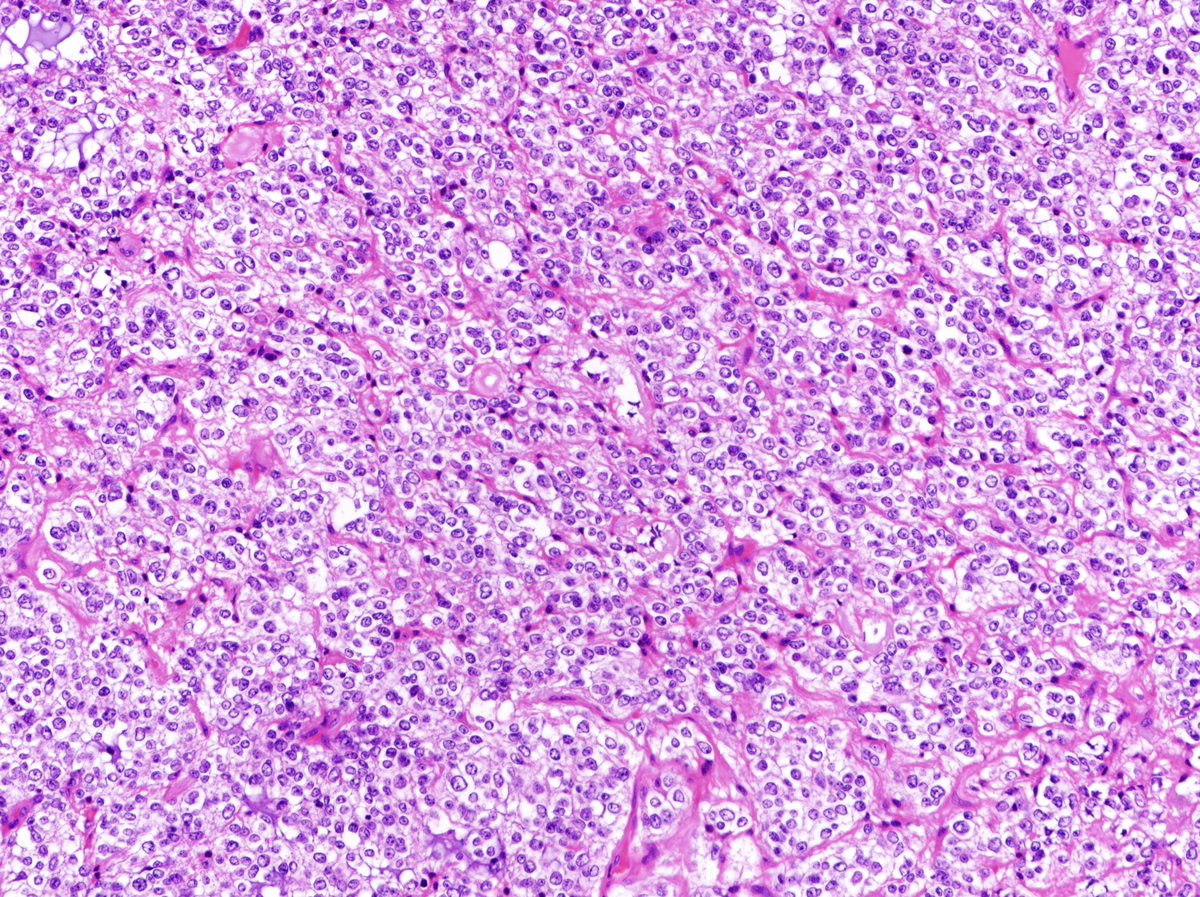

Usually located at the edge of the testis and displacing its parenchyma, metastatic tumors can mimic a primary testicular malignancy. This is an example of desmoplastic small round cell tumor (DSRCT). Confirmed EWSR1 FISH. @GUpath @urology

Andres_Matoso's tweet image. Usually located at the edge of the testis and displacing its parenchyma, metastatic tumors can mimic a primary testicular malignancy. This is an example of desmoplastic small round cell tumor (DSRCT). Confirmed EWSR1 FISH. @GUpath @urology